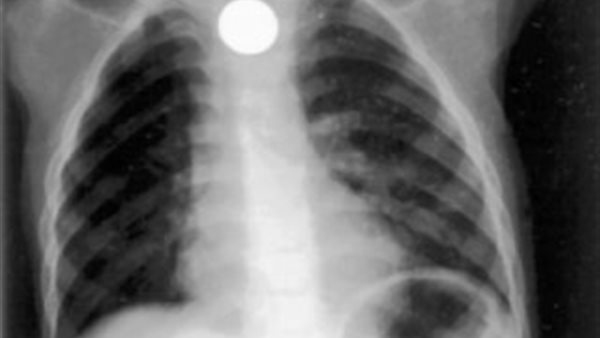

وبحسب الصحيفة، عند تشخيص حالته وجد الأطباء أنه كان يعاني من حالة نادرة ومعقدة تسمى انثقاب المريء، أو تمزق في أنبوب الطعام، وقال الأطباء إن تلك الإصابة تسببت في تسرب في رئتيه، مما أدى إلى الانصباب الجنبي والالتهاب الرئوي القصبي.

ابتلع طفل في مدينة دلهي الهندية، يبلغ من العمر 8 سنوات عملة معدنية، تسببت له في سعال متكرر وسيلان اللعاب، وأحدثت له مضاعفات خطيرة، من بينها إصابته بتمزق في المريء وكذلك تسريب في الرئتين، وفقًا لـ تايمز ناو.